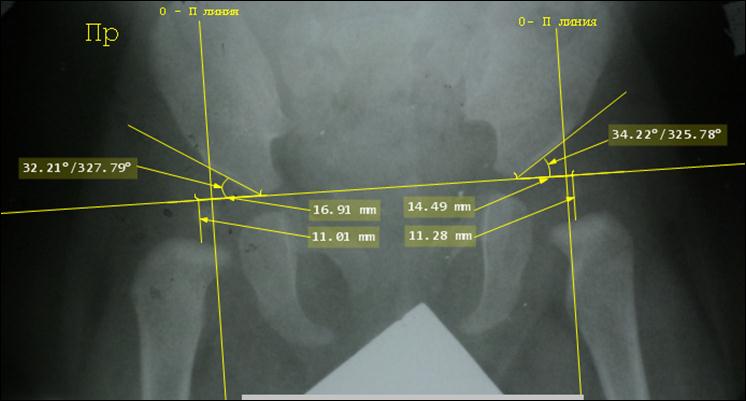

Снимок

ребенка 7 месяцев, расчерчивание по Хильгенрейнеру. Двухсторонняя дисплазия

тазобедренных суставов с децентрацией: обратите внимание на вертикальные и

горизонтальные позиции, ацетабулярные углы

и положение ядер окостенения головок относительно линий Омбредана - Перкинса.

Постановка диагноза запоздалая. Назначено консервативное лечение с помощью

отводящей шины БелНИИТО (она применяется

редко и не имеет преимуществ перед другими).

Тот

же ребёнок. Уже через неделю ортезирования ножки приняли положение Лоренц I. Сделан снимок с ортезом: оси шеек обеих бедер чётко

направлены в центр вертлужных впадин, подтверждено вправление головок обеих

бедер. Использование ортеза продолжено

еще 3 месяца.

Предыдущий

снимок мы специально расчертили по

Хильгенрейнеру: показатели центрации головок не в норме, хотя ядра окостенения

находятся кнутри от линий Омбредана – Перкинса. Потому не следует применять

схемы Хильгентейнера и Рейнберга для определения центрации головок на снимках в

ортезе.

Через

3 месяца, в возрасте 10 месяцев, была сделана контрольная рентгенограмма без

ортеза, на которой все

рентгенометрические параметры значительно выходили за пределы нормы:

ацетабулярные углы превышали 30° с обеих

сторон, ядра окостенения головок бедер

не полностью покрывались крышами вертлужных впадин и большая их часть

находилась кнаружи от линий Омбредана – Перкинса. Ортезирование продолжено

ещё на 4 месяца.